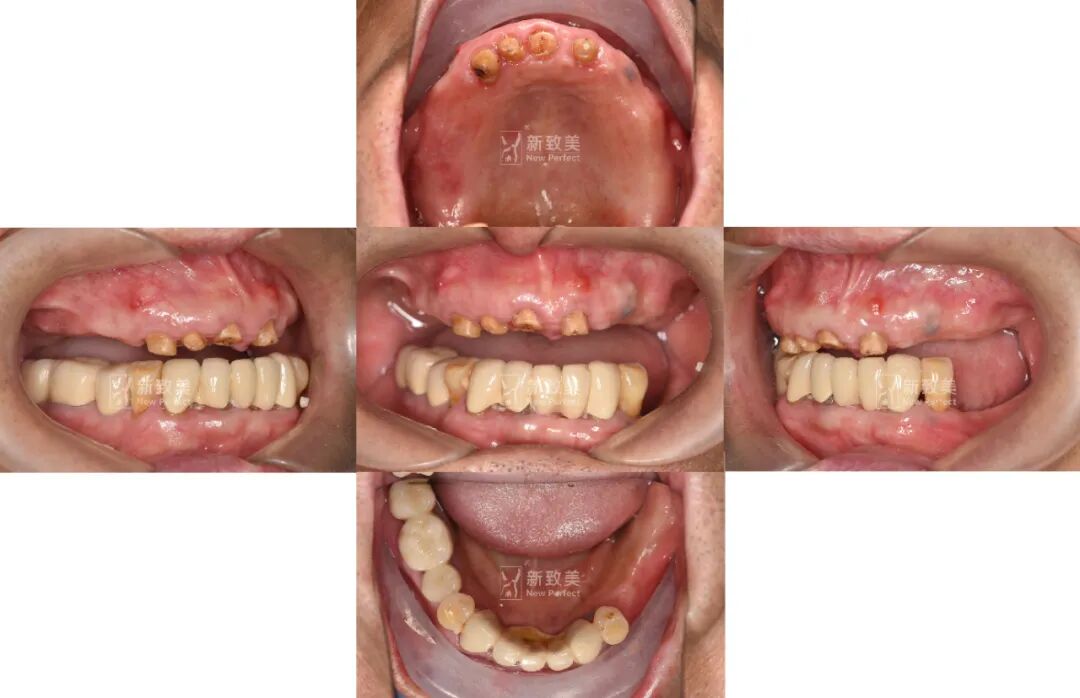

1、基本資料

•  基本資料:趙先生,男, 69歲,體??;上頜多顆牙缺失,牙位13、1211、21留有殘根,長期佩戴傳統(tǒng)活動假牙,大聲說話時活動假牙易脫落,且咀嚼效率低下;下頜常規(guī)固定修復(fù),牙位35、36、37缺失。

• 主訴:上頜傳統(tǒng)活動假牙固位不好,要求種植修復(fù)。

• 治療方案:經(jīng)過充分溝通確定,上頜采用數(shù)字化種植導(dǎo)板輔助植入,拔除剩余殘根,即拔即種+即刻修復(fù);下頜缺失牙位擇期常規(guī)種植修復(fù)。

【術(shù)前照片】

7、術(shù)后戴牙照片

8、戴牙前、后對比

本次案例應(yīng)用數(shù)字化種植導(dǎo)板輔助定位植入,手術(shù)過程非常順利,即拔即種在時間上也有很大的優(yōu)勢,拔除壞牙同時植入人工牙根,可以節(jié)省就診時間,縮短種植牙療程,減少痛苦,讓患者手術(shù)當(dāng)天就能重新?lián)碛腥笔У难例X,恢復(fù)了部分咬合功能和美學(xué)效果,受到了患者的夸贊與好評!